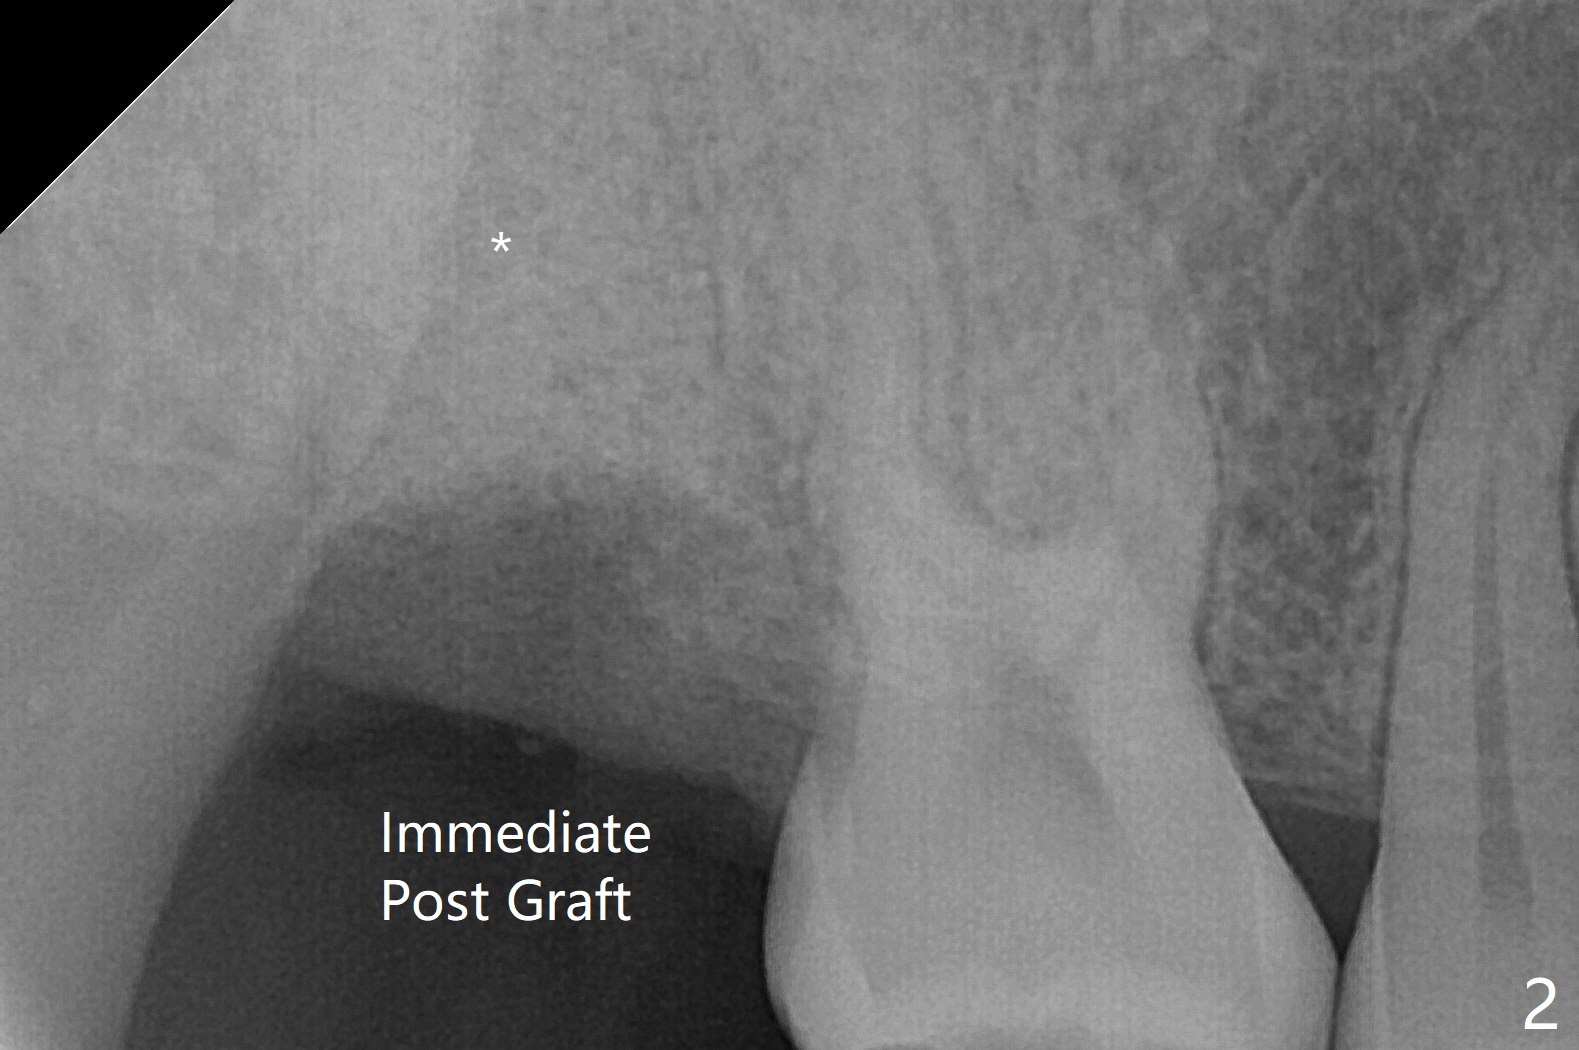

31岁女去年10月份就诊,右上7隐裂(图一),提出根管治疗,牙冠或者拔除,植牙。她犹豫不决,因为今年6月份回国。昨天因腭侧脓肿深度牙周袋复诊,最后同意拔除,植骨。使用GEM21S(血小板因子,没有时间抽血)与皮质骨粉(加一些人工骨)调袢(图二:*),覆盖不可吸收膜(Cytoplast,一张~$50,剪半可用于两个磨牙牙槽窝,买一盒十张,赠送两个PTFE缝线(最近促销);图三)。PTFE,Cytoplast以及Plumber tape据说来自同一个材料,至少前两者最好同时用。但是这个病例,助手打开PGA缝线后,我们才知道Cytoplast刚刚到,它的好处在于暴露于口腔,下面骨粉几乎不会感染。五周后撤除 ,下面骨粉一般愈合正常,接近百发百中。想不到垂直距离特别短,没有空间放置空间保持器,后者有利于牙周敷料固定,下颌第二磨牙牙尖咬到保持器攀(loop),尽管保持器已经放置第一磨牙颈部。无可奈何,在缝线周围涂牙周胶水(图三:蓝紫色)。术后两周膜已经脱落(图四),但是下面骨粉好像没有丢失太多(图五)。两周后伤口愈合(图六)。骨粉失去不多(图七)。